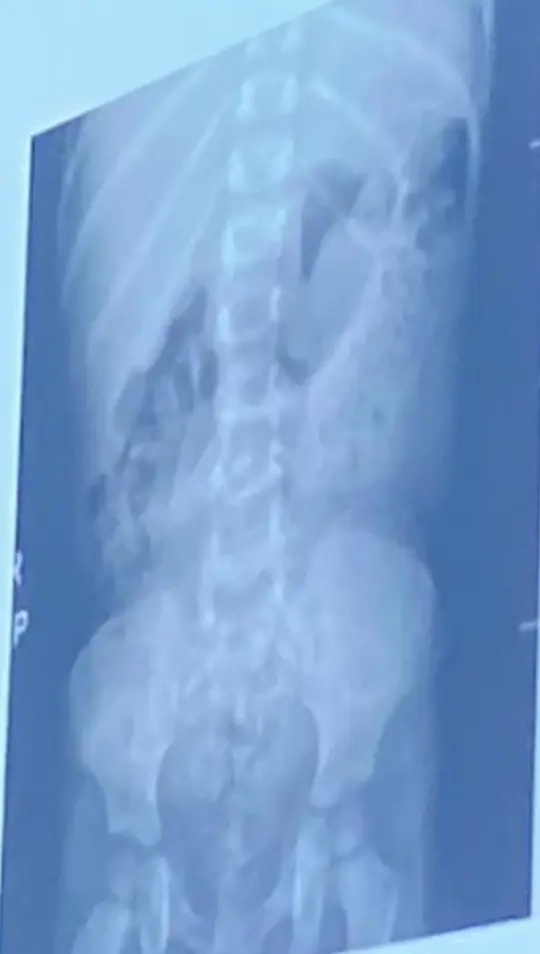

Vesicoureteral Reflux (VUR)

History:

- Recurrent UTIs

Modality:

- MCUG (micturating cystourethrogram)

Findings:

- Posterior urethral valve

- Dilated ureters

- Tortuous ureters

- Dilated ureteric pelvis bilaterally (hydronephrosis)

Diagnosis & Grading

- Studies: Renal US (Typically first); MCUG (to confirm diagnosis); RNC (for follow-up).

International Grading System (MCUG Findings):

| Grade | Description / Findings |

|---|---|

| Grade I | Into a nondilated ureter only. |

| Grade II | Into the pelvis and calyces without dilation. |

| Grade III | Mild to moderate dilation of ureter, pelvis, and calyces; minimal blunting of fornices (become close). |

| Grade IV | Moderate ureteral tortuosity and dilation of pelvis and calyces (adhered to each other). |

| Grade V | Gross dilation; significant tortuosity; loss of papillary impressions; blunting of calyces. |

Risk Factors:

- Congenital

- Holding voiding

- Chronic constipation

- Recurrent UTI

Complications:

- Renal scarring

- Hypertension

- End-stage renal failure

Management:

- Antibiotic prophylaxis

- Surgery for grades 4-5

Posterior Urethral Valve (PUV)

- MCUG / VCUG (voiding cystourethrogram) only in boys

- Dilated proximal urethra

- Dilated ureter

- Dilated bladder

- Dilated posterior urethra

Only in boys

Can be diagnosed antenatal and prevented!

- Renal failure

- UTI

Treatment:

- Surgical removal of the valve

- Catheter or drain procedure as temporary measure